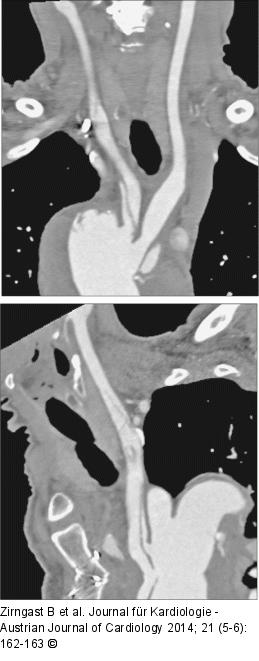

Abbildung 3: A. carotis communis

Dissektion der A. carotis communis dextra et sinistra |